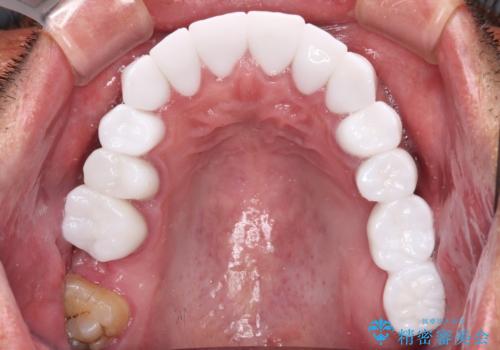

本来、あまりにも不自然な歯となるため、フルジルコニアクラウンを前歯に使用することは、咬合力が強すぎる場合を除き、ほとんどありません。

それでも、色調、形態ともに不自然なくらい真っ白な歯をご希望でしたので、患者様には大変満足していただきました。